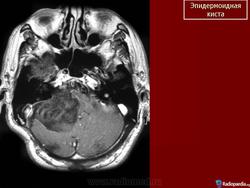

Эпидермоидная киста